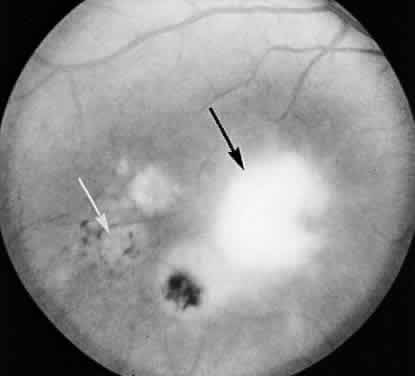

The expense and inconvenience of using nonhuman primates led to the renewed interest in rodent models of disease. Pavesio and associates54 were able to produce multifocal toxoplasmic retinochoroiditis in hamsters consistently after intraperitoneal inoculation of the ME49 strain of T gondii. Animals develop multiple foci of retinitis that resolve spontaneously without treatment. After resolution of lesions, tissue cysts can be found in the retina (Fig. 3). This model may prove to be useful for the study of T gondii infections of the retina at a cellular level and may ultimately be useful for studying the efficacy of cysticidal drugs as they become available. This model will be less useful for studying the natural history of human disease, however, because the number, distribution, and appearance of lesions are not reminiscent of those seen in human beings.

Fig. 3. Light micrograph of a hamster eye after resolution of ocular toxoplasmosis. A large tissue cyst is seen in normalappearing retina (hematoxylin and eosin). (Courtesy of Barbara A. Nichols, PhD.)